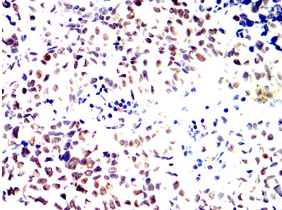

IHC    1/200 - 1/1000